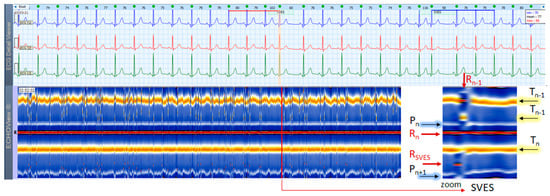

3.2. NSR, SVES, VES Cases

This section interprets together 3-lead Holter ECG strips and the corresponding ECHOView images (ECG lead 1) of two patients in sinus rhythm with frequent supraventricular (Figure 4) and ventricular extrasystoles (Figure 5). Detailed interpretation of the zoomed ECHOView color map in the area of interest around one extrasystole is presented in the caption of the figures. In general, SVES and VES can be easily recognized as occasional narrow vertical lines of a different color from the background color map presented by NSR. In the zoomed ECHOView images, we can identify important SVES and VES differences vs. sinus rhythm beats, such as the early non-sinus ventricular depolarization visible as a red dot in the blue horizontal area between T-waves and P-waves (Figure 4 and Figure 5); typically for VES morphological alterations—the wider R-waves, the black spots with ST-segment depression and the T-wave electric axis inversion (Figure 5). Despite ECHOView being useful for the localization of vertical lines of extrasystoles at a glance, the ECG trace is mandatory to verify their type.

4.3. ECHOView: Summary of the Principles of Imaging

The color-coded ECG amplitudes of sequential beats produce an intuitive trace of different intervals (PnRn, RnTn, Rn−1Rn, RnRn+1, etc.) in a visible image (width × height = 1740 beats × 1500 ms) within one ECHOView page. Without a specific measurement, this visual effect resembles the rendering of one-dimensional time trends of automatically measured ECG intervals. These trends show stable PnRn and RnTn intervals during the NSR part of the examples in Figure 4, Figure 5, Figure 6, Figure 7, Figure 8, Figure 9, Figure 10, Figure 11 and Figure 12. The trends are also informative for the RR-intervals (Rn−1Rn, RnRn+1) on a beat-by-beat basis that is helpful for identifying long-term HR changes in high-rate SINT (Figure 6, Figure 7 and Figure 8) and AFL (Figure 15), as well as rhythm, transitions NSR→ paroxysmal SVA (Figure 9), NSR→PSVT (Figure 10, Figure 11 and Figure 12), NSR→NSVT (Figure 10, Figure 11 and Figure 12), and AF→AFL→ST (Figure 16).